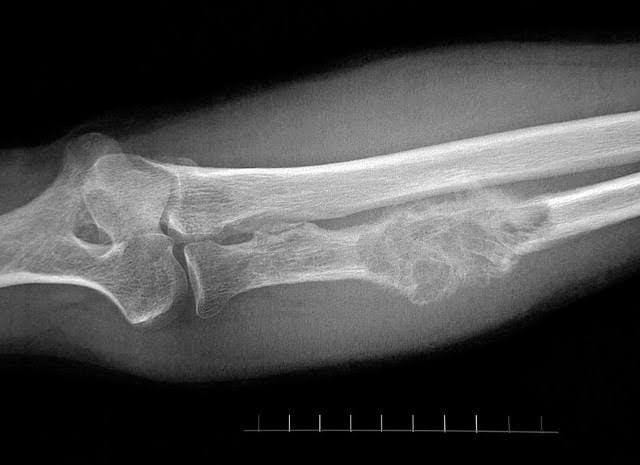

7. Manusia telah mengetahui cara mengobati patah tulang sejak ribuan tahun lalu

Manusia sudah punya masalah patah tulang sejak mereka hadir di Bumi. Namun, menurut jurnal Clinical Orthopaedics and Related Research yang dirilis pada 2009 menyatakan bahwa manusia juga telah mengetahui cara mengobati patah tulang sejak lama.

Sebagai contoh, menurut catatan Mesir Kuno sekitar tahun 1600 SM, dijelaskan cara masyarakat saat itu merawat patah tulang, misalnya tangan patah. Direkomendasikan untuk menyatukan patahan tulang, lalu membungkusnya dengan jerami.

Selain itu, berdasarkan dokumen medis Yunani Kuno sekitar 440-340 SM, penulisnya menjelaskan teknik merawat patah tulang dengan membungkusnya dengan jerami lalu merendamnya dalam minyak dan lilin.